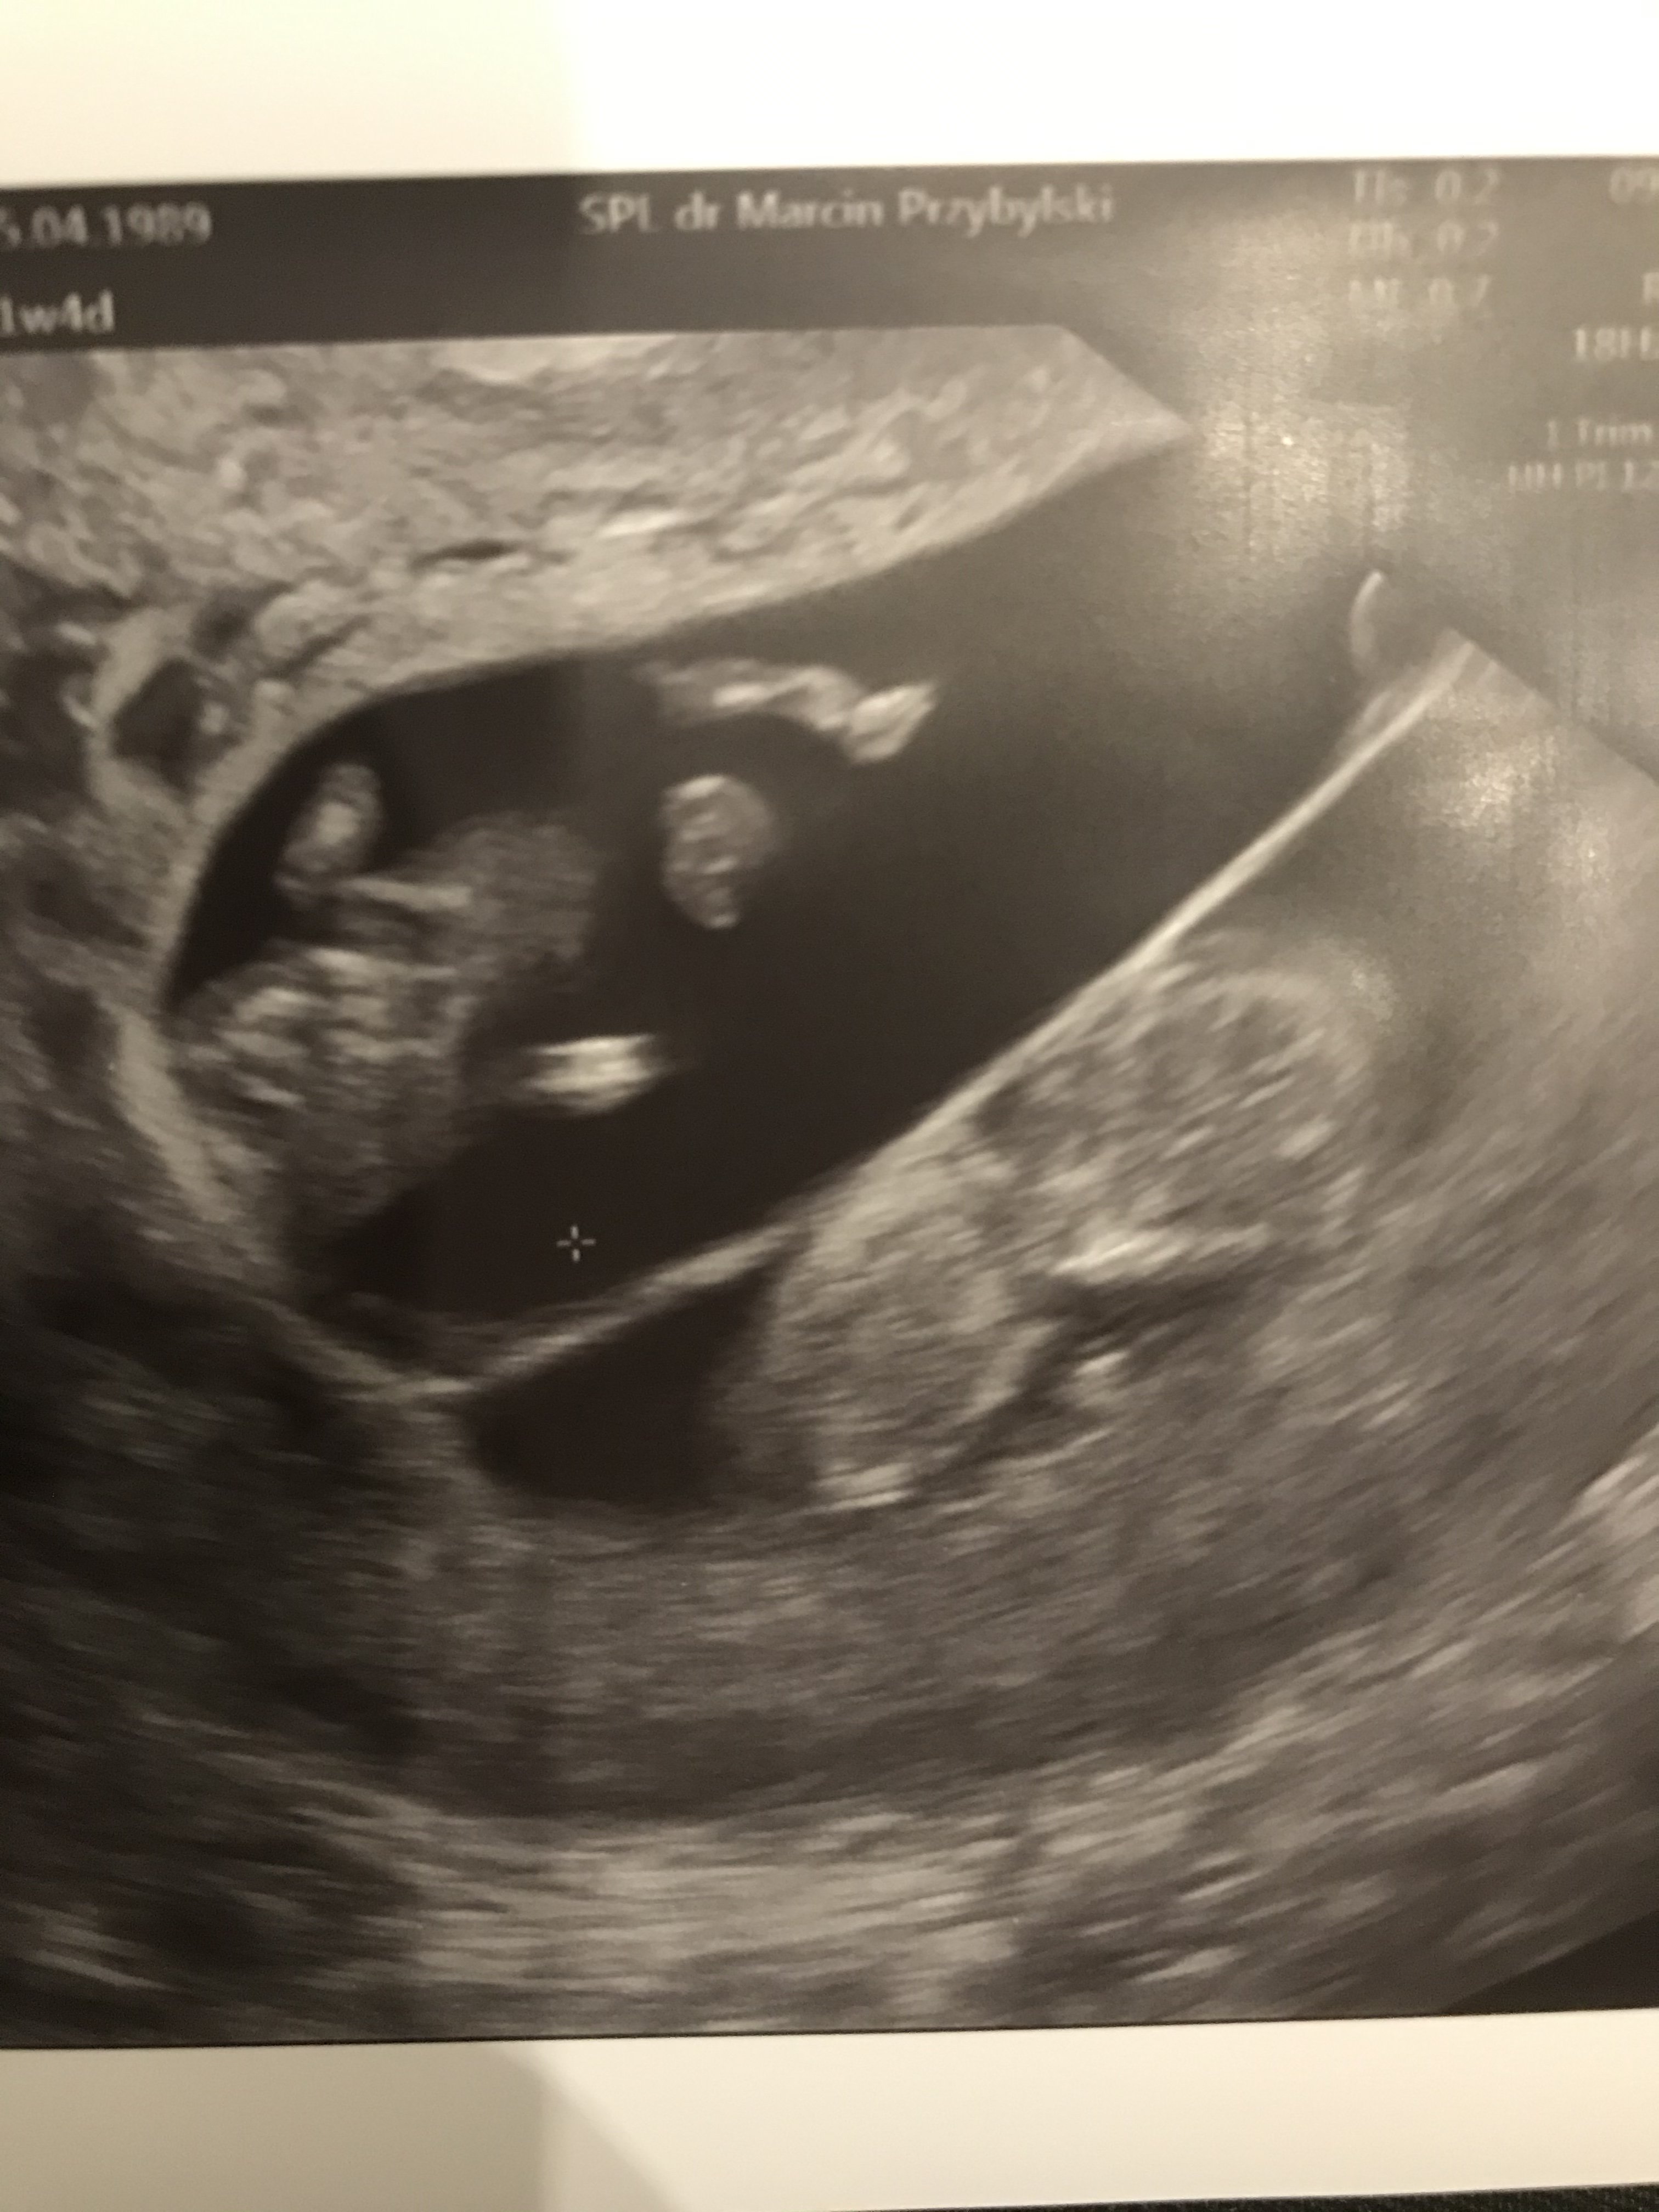

CudaA to moje dwa łobuzy![]()